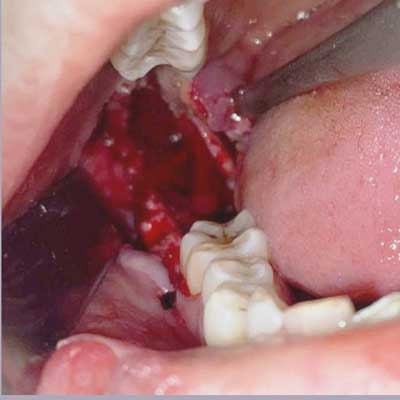

The entire cyst was removed in-toto using an intra-oral approachalong with the offending tooth. There was no external skin incision and the healing was uneventful.

Odontogenic Cyst 3

Here we can see the entire cyst with its lining along with the tooth to which it was attached. Histopathological evaluation of the cyst revealed it to be an Odontogenic Keratocyst.